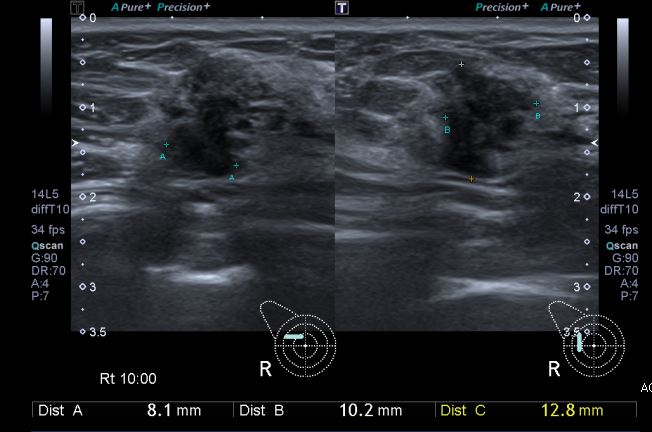

건강검진상 이상 소견으로 내원하신 40대 여성 분으로 우측 10:00 방향의 의심스러운 혹 중심핵생검 시행하여 우측 침윤성 유관암 진단 되었습니다.